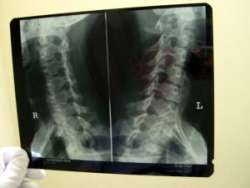

Dlhodobé bolesti chrbta môže spôsobovať aj ochorenie, ktoré lekári objavili u Slovákov iba prednedávnom. Ide o tzv. axiálnu spondylitídu, ktorá postihuje mladých ľudí v produktívnom veku do 40 rokov. "Základným príznakom ochorenia je bolesť chrbta pretrvávajúca viac ako tri mesiace. Aj preto sme si ešte pred niekoľkými rokmi mysleli, že ide o bežnú bolesť chrbta. Teraz sa však prišlo na to, že ide o úplne nové ochorenie, spojené so zmenami na chrbtici a v oblasti panvy," uviedol primár Národného ústavu reumatických chorôb Jozef Lukáč.

Na diagnostiku a potvrdenie ochorenia je potrebné vyšetrenie pacienta prostredníctvom magnetickej rezonancie, ktorá potvrdí zmeny na chrbtici a skĺbenia panvových kostí. "V skoršom štádiu nám časť pacientov dobre reaguje na liečbu bežnými protizápalovými liekmi, u mnohých pacientov, najmä v neskoršom štádiu ochorenia, je však už táto liečba neefektívna a ich chrbticu poznačia zmeny, ktoré už nie je možné liečbou ovplyvniť. Bohužiaľ veľké percento pacientov tak ostávala na invalidnom dôchodku," povedal Lukáč.